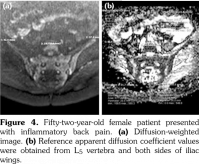

All patients underwent MRI at 1.5-Tesla superconducting eight channel MRI system (Achieva, Philips Medical Systems, Best, The Netherlands) provided with high-speed gradients. The following sequences of sacroiliac joints in the oblique coronal and axial planes as the standard protocol were obtained in the supine positions with a high-resolution phased-array coil: turbo spin-echo T1-weighted (repetition time/echo time, 600/minimum), turbo spin-echo T2-weighted (repetition time/echo time, 2100/80), T2-weighted spectral presaturation with inversion recovery (SPIR) (3100/70), T1-weighted SPIR (600/ minimum) with and without gadolinium-based contrast agents (0.1 mmoL/kg of body weight). All sequences contained lower lumbar spine (Figures 1a-c).

Diffusion-weighted imaging was performed by single-shot spin-echo echo-planar imaging technique with diffusion gradient b values of 0 and 600 s/mm2 (Figure 1d). The following DWI parameters were used: field of view: 25 (right-left) x 32 (anteroposterior) cm; number of excitations: 2; matrix size: 176x176; slice thickness: 4 mm; repetition time/echo time, 8000/minimum; intersection gap: none.

Sacroiliac joints were assessed according to ankylosing spondylitis criteria. Before evaluation of standard MRI protocol, patients’ information was removed from images. Afterwards, two experienced radiologists evaluated the images for the presence of inflammatory activity twice at separate sessions to assess interobserver variability. Following the examination of T2-weighted SPIR, contrast- enhanced T1-weighted SPIR, and DWIs at b values of 600 s/mm2, two radiologists and rheumatologists reached a consensus on the disease activity in the light of positive features of Berlin criteria. The DWIs were transferred to a separate workstation (Phillips, Extended MR workspace, 2.6.3.2.HF3, Netherlands). ADC maps were generated. T2-weighted SPIR images, contrast-enhanced images and diffusion-weighted images with ADC maps were put on the screen side by side. In the disease group, the hyperintense lesions on T2-weighted SPIR images and enhanced focuses on contrast- enhanced images were noted and the same lesions were marked on DWI images and ADC map. A circular ROI with a range of 40-75 mm2 was placed in those areas. In the control group a circular ROI was placed in the subarticular area of joints. Also, the same process was performed for the normal-appearing bone marrow areas near the joints of the disease group (Figure 2). Four standard measurements were conducted from each joint, including two on sacral and the other two on the iliac side for all patients (Figure 3). Additionally, two measurements were conducted from the fifth lumbar vertebra and one from each iliac wing (Figure 4). All measurements were performed twice. ADC values were expressed as square millimeters per second. The r-ADC ratio was calculated by dividing ADC value of subchondral bone or inflammatory lesions to ADC values of the fifth lumbar vertebra and iliac wings.